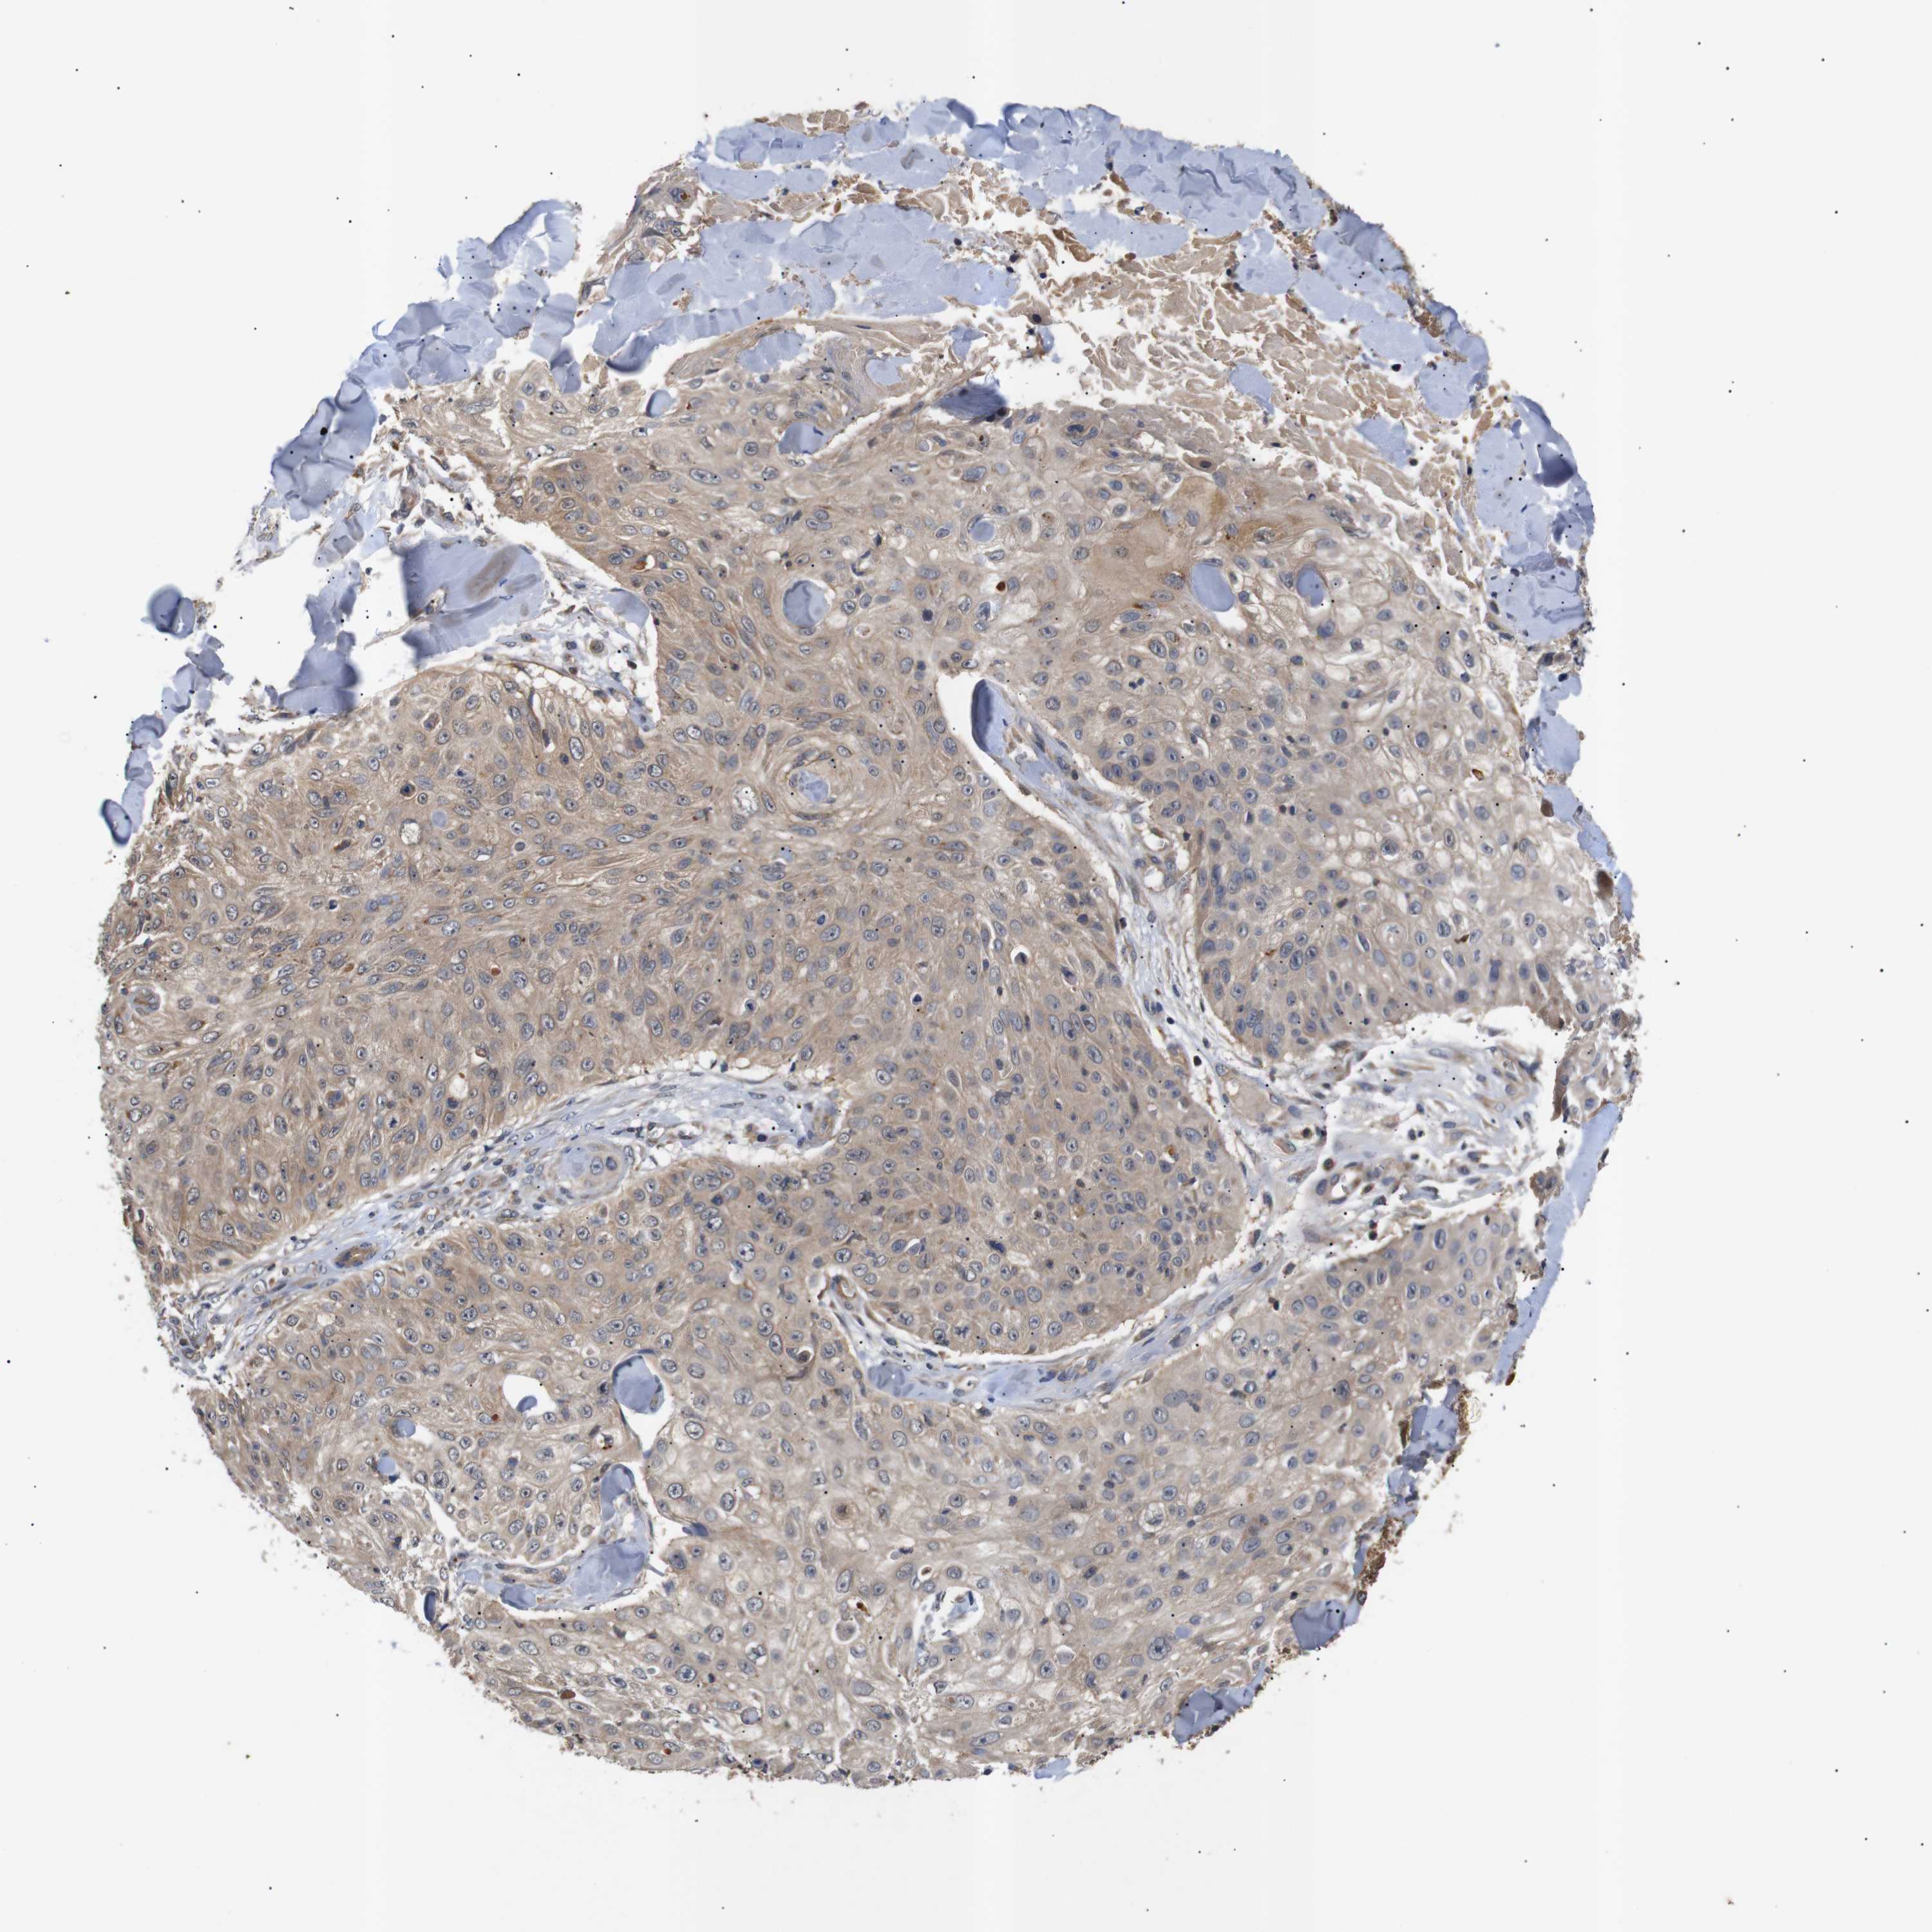

SKIN CANCER - Protein expressioni

A mouse-over function shows sample information and annotation data. Click on an image to view it in a full screen mode. Samples can be filtered based on level of antibody staining by selecting one or several of the following categories: high, medium, low and not detected. The assay and annotation is described here.

Each image is clickable and will lead to virtual microscopy that enables deeper exploration of all samples and also displays staining intensity scores, fraction scores and subcellular localization as well as patient and tissue information for each sample.

Antibody HPA015257

High

Strong

>75%

Location

Squamous cell carcinoma in situ, NOS

Squamous cell carcinoma, NOS